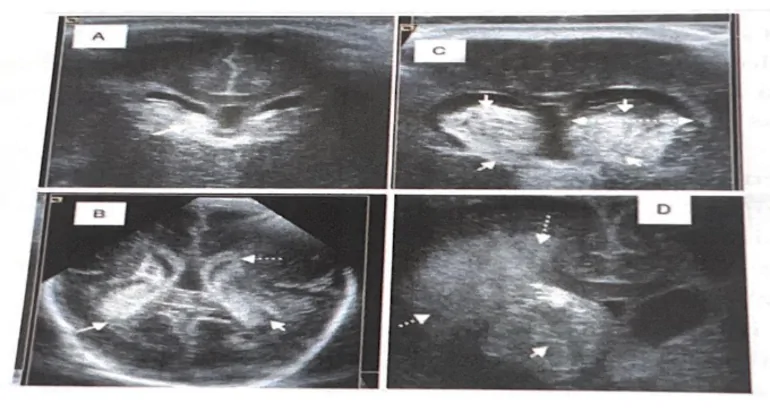

Among the ICHs that occur in the PNB are included germinal matrix hemorrhage (GMH), intraventricular hemorrhage (IVH) and parenchymal hemorrhages, the latter being the least frequent. Both GMH and IVH can be grouped under the term peri-intraventricular hemorrhage (PV-IVH) and it is the main complication that can lead to brain injury in the PNB.

The most frequent origin of hemorrhages in the PNB’s brain is the germinal matrix (GM), a structure located in the periventricular subependymal region that is highly vascularized. When a GMH occurs, it can rupture the underlying ependyma and penetrate into the ventricles, thus constituting IVH (Ballabh, 2014)

PV-IVH is classified into different grades defined by the presence or absence of hemorrhage in the ventricles, the percentage of intraventricular hemorrhage, and the presence or absence of periventricular hemorrhagic infarction.

- Grade I: the hemorrhage is localized in the subependymal GM,

- Grade II: there is intraventricular blood occupying less than 50% of the ventricle area and without ventricular dilation,

- Grade III: there is intraventricular blood occupying more than 50% of the ventricle area and with ventricular dilation.

- Grade IV: intraventricular and intraparenchymal hemorrhage, corresponding to periventricular venous hemorrhagic infarction.

Hemorrhage at this level will cause a loss of its cellular progenitors and, due to the pressure caused by the hemorrhage and the resulting oxidative stress, the lesion of the surrounding WM will be aggravated, contributing to periventricular leukomalacia (PVL) (Cerisola et al., 2019.